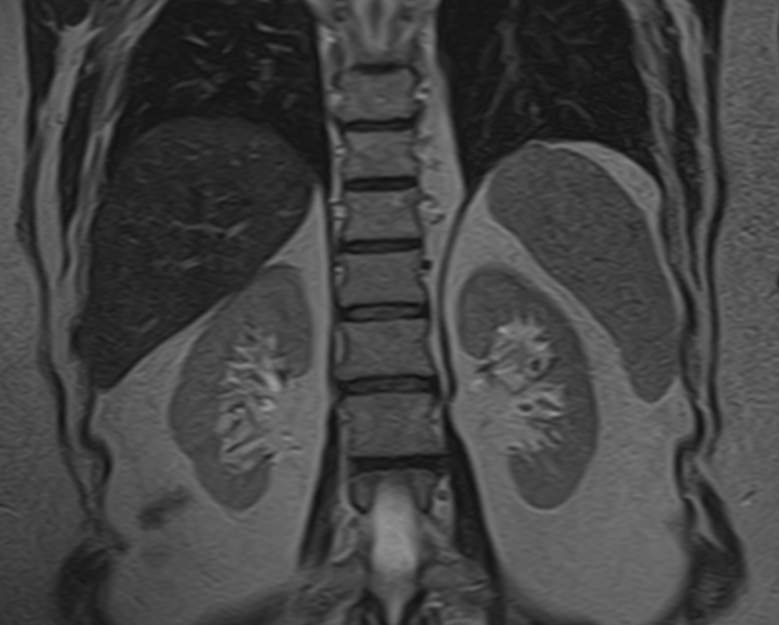

МРТ забрюшинного пространства является наиболее информативным, безопасным и доступным методом исследования, который позволяет оценить состояние органов, расположенных в данной анатомической зоне (почки, надпочечники, мочеточники), выявить возможные патологические процессы.

В клинике «Доступная медицина» установлен новейший высокопольный томограф экспертного уровня TOSHIBA VANTAGE TITAN 1,5 Тесла, на котором выполняется обследование органов забрюшинного пространства. За счет высокой индукции магнитного поля аппарат при сканировании создает изображения на плоскости превосходной четкости, затем с помощью компьютерных приложений данные преобразуются в изображения трехмерного формата, что обеспечивает точность и достоверность диагностики.

- Почки. С помощью магнитно-резонансной томографии удается диагностировать структурные изменения. Аномалии развития, воспалительные процессы, изменение нормального расположения в забрюшинном пространстве.

- Надпочечники. Парный орган эндокринной системы. Из-за особенностей анатомии, строения, трудно визуализируются прочими способами. МРТ позволяет получить детальную картину изменений надпочечников.

Полученные по итогам изображения позволяют выявить все возможные структурные патологии на ранней стадии. Это плюс, поскольку многие расстройства эффективно корректируются только на начальном этапе.